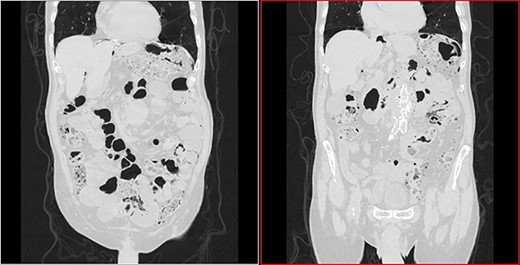

He arrived at the emergency department walking and with no clinical distress. He was complaining of hematuria for a month and worsening of chronic constipation in the last 2 days. Physical examination demonstrated discrete abdominal distention. Laboratory tests showed normal c-reactive protein (CRP), white blood cell count and lactate level. A new CT revealed no change in the previous findings: intestinal pneumatosis and pneumoperitoneum (Figs 2 and 3).

Transversal CT image in lung window showing pneumoperitoneum and pneumatosis intestinalis.